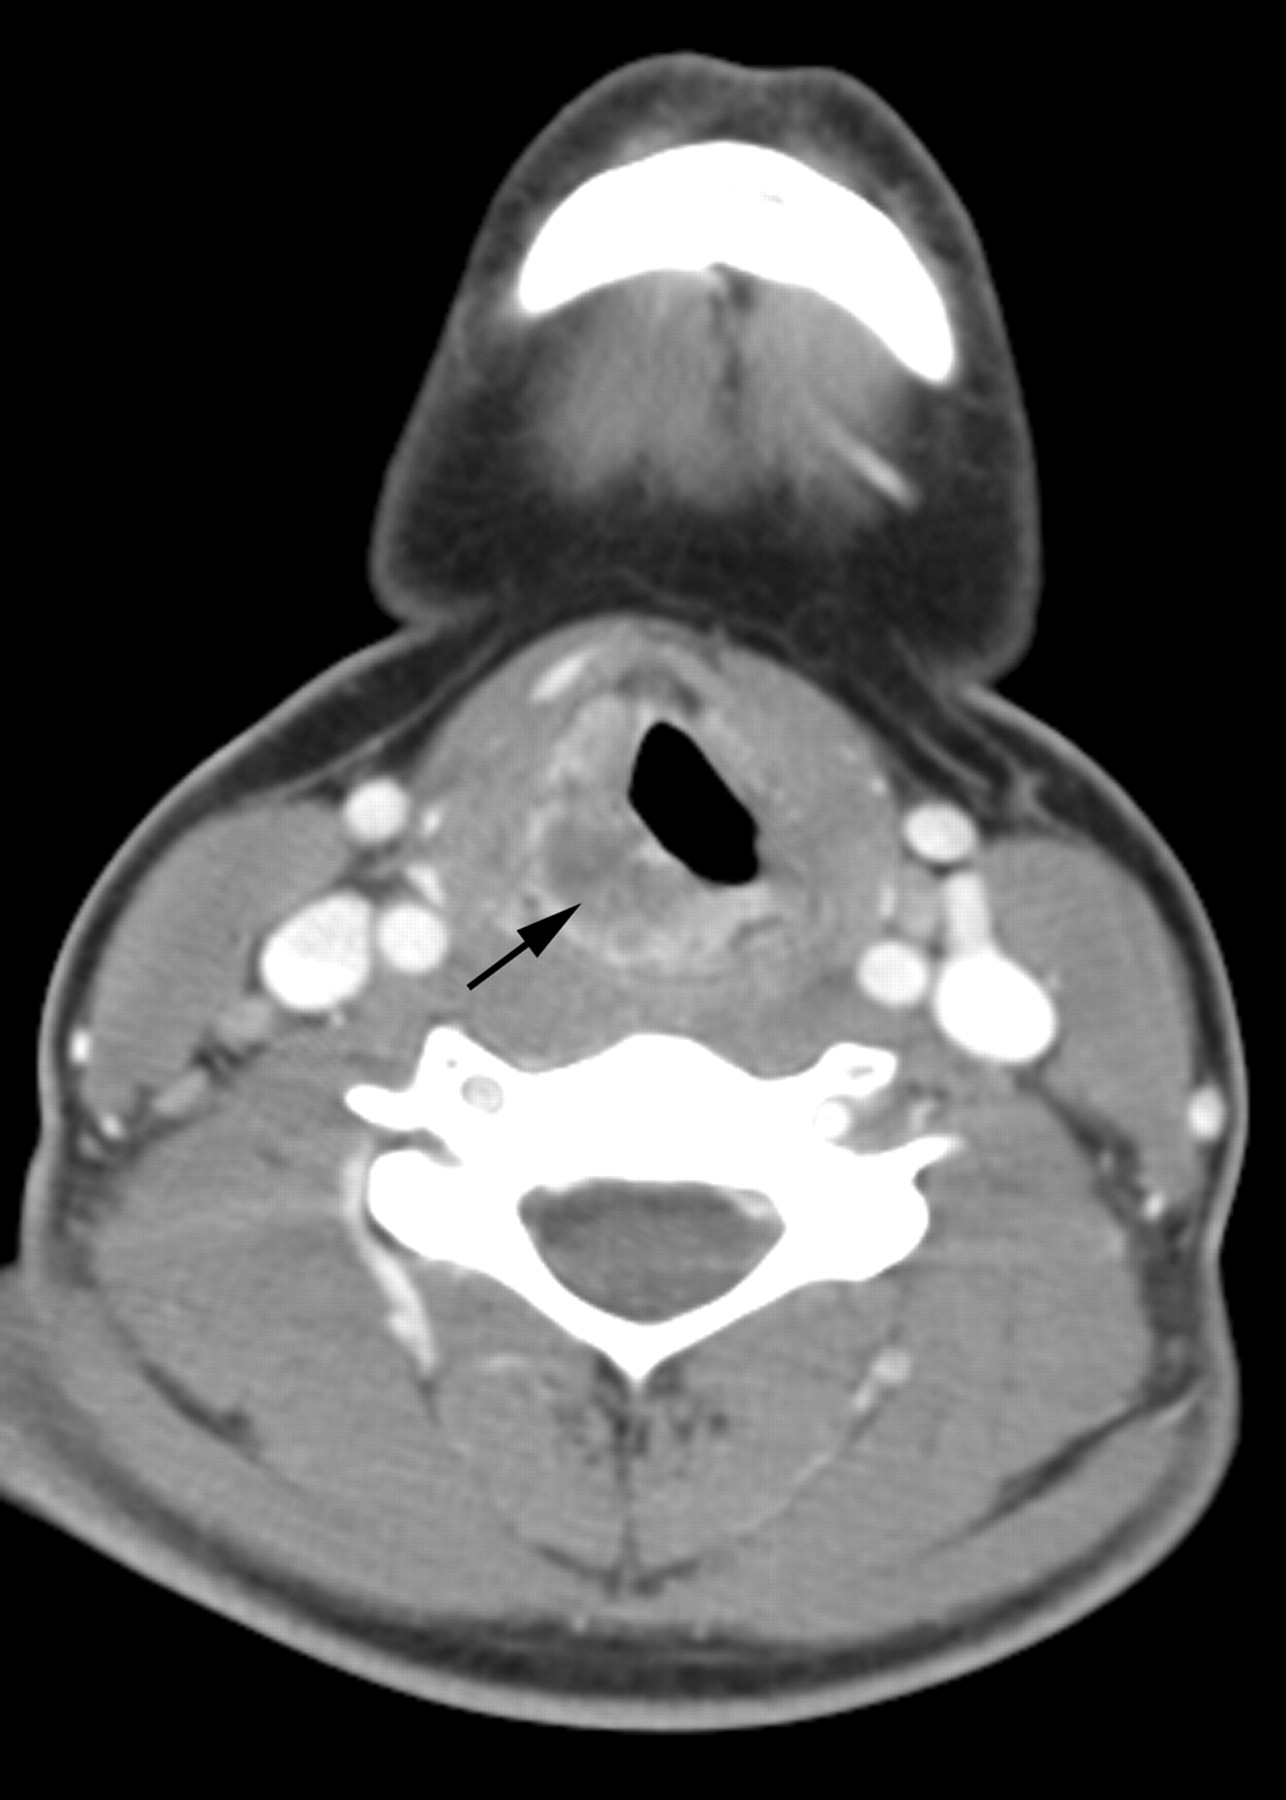

A 14-year-old adolescent girl presented with a 4-month history of hoarseness and sore throat and a 1-month history of odynophagia and dysphagia. Clinical examination revealed a mass at the level of the glottis on the right. Contrast-enhanced CT scan (Fig 2) and MR imaging revealed a 28-mm × 13-mm × 31-mm irregular and heterogeneously enhancing, submucosal mass involving the right side of the epiglottis and aryepiglottic fold, extending inferiorly to involve the right side of the larynx. The mass exhibited a relatively short T2 relaxation time but was hyperintense relative to muscle, with the pulse parameters used on the FSEIR images. There were mildly asymmetric, enhancing ipsilateral level IV and V lymph nodes that did not meet size criteria for pathologic enlargement. On fiberoptic examination, the mass appeared to be bulging into the right pyriform sinus, causing fixation of the right vocal cord, with minimal subglottic extension. Results of biopsy revealed a well-differentiated invasive squamous carcinoma. The tumor was classified as T3N0M0. Fresh tissue was not submitted for karyotypic analysis; results of paraffin-embedded tissue was negative by FISH for t(15;19). In situ hybridization for EBER was not performed.

Patient 2. Carcinoma of the larynx. Contrast-enhanced CT scan of the neck demonstrates an irregular and heterogeneously enhancing, off-midline submucosal mass (arrow) involving the right side of the larynx.